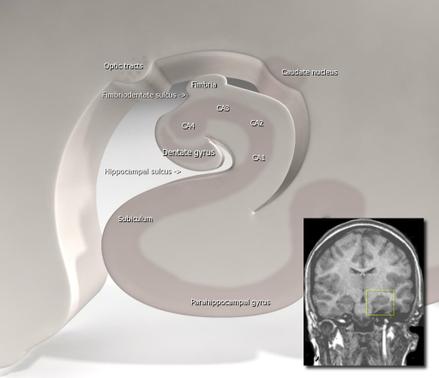

Tal como demostró Joseph Altman en 1965 y se reconoció cuarenta años más tarde, hay zonas del cerebro (subventricular y subgranular del giro dentado del hipocampo) en las que siguen naciendo nueva células neurales. Hay neurogénesis. Cajal estaba equivocado.

La neurogénesis de hipocampo está favorecida, dinamizada por un factor de crecimiento, el BDNF (Brain-Derived Neurotrophic Factor). Si hay depresión hay menos BDNF. Si hay poca serotonina hay poco BDNF. Si subimos la serotonina con los famosos inhibidores de la recaptación de serotonina (Prozac y similares, para entendernos) se recupera el BDNF y la neurogénesis.

El hipocampo es una zona cerebral fundamental para la memorización de lo que sucede, novedoso y relevante, dónde se produjeron eventos interesante, qué señales ayudan a rememorarlos. El individuo recolecta en la cesta del hipocampo novedades, nuevas experiencias, nuevos conceptos… Durante el sueño se produce el trasiego de lo novedoso a las áreas de la memoria consolidada, a las que toman decisiones basadas en el conocimiento integrado a lo largo del tiempo.